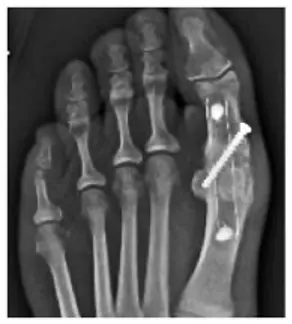

Extremities

Pre-contoured anatomic plates for hand, foot & ankle applications, cannulated implants for proximal interphalangeal fusions, and wedges for osteotomies are examples where PEEK-OPTIMA polymers can drive superior performance, including:

- Bioinert and biocompatible with modulus of elasticity close to cortical bone

- Radiolucency allowing for a more accurate assessment of fusion3

- Improved patient satisfaction4

- Improved level of direct bone contact in as early as 4 weeks5

- New bone formation as early as 6 weeks6

10.Image: CFR-PEEK composite fusion plate X-ray image, courtesy of Carbofix.